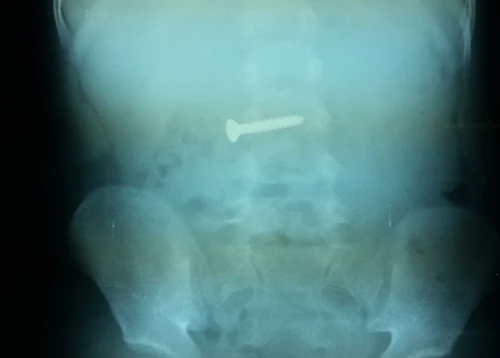

Trước đó, vào sáng cùng ngày, người nhà đã đưa một bé trai 3 tuổi (trú xã Lộc Ninh, TP.Đồng Hới) vào bệnh viện này cấp cứu. Qua thăm khám, chụp phim, các bác sĩ đã phát hiện một chiếc đinh vít xoắn dài khoảng 3 cm nằm trong ổ bụng cháu bé.

Theo người nhà cháu bé, chiếc đinh này đã trôi tuột vào cổ họng của cháu sau khi cháu nhặt được ở nền nhà và bỏ vào miệng ngậm.

May mắn cho cháu là chiếc đinh vít lọt vào thực quản xuống ruột nên không nguy hiểm đến tính mạng, không phải phẫu thuật mà chỉ cần theo dõi đồng xu ra ngoài theo đường tiêu hóa.